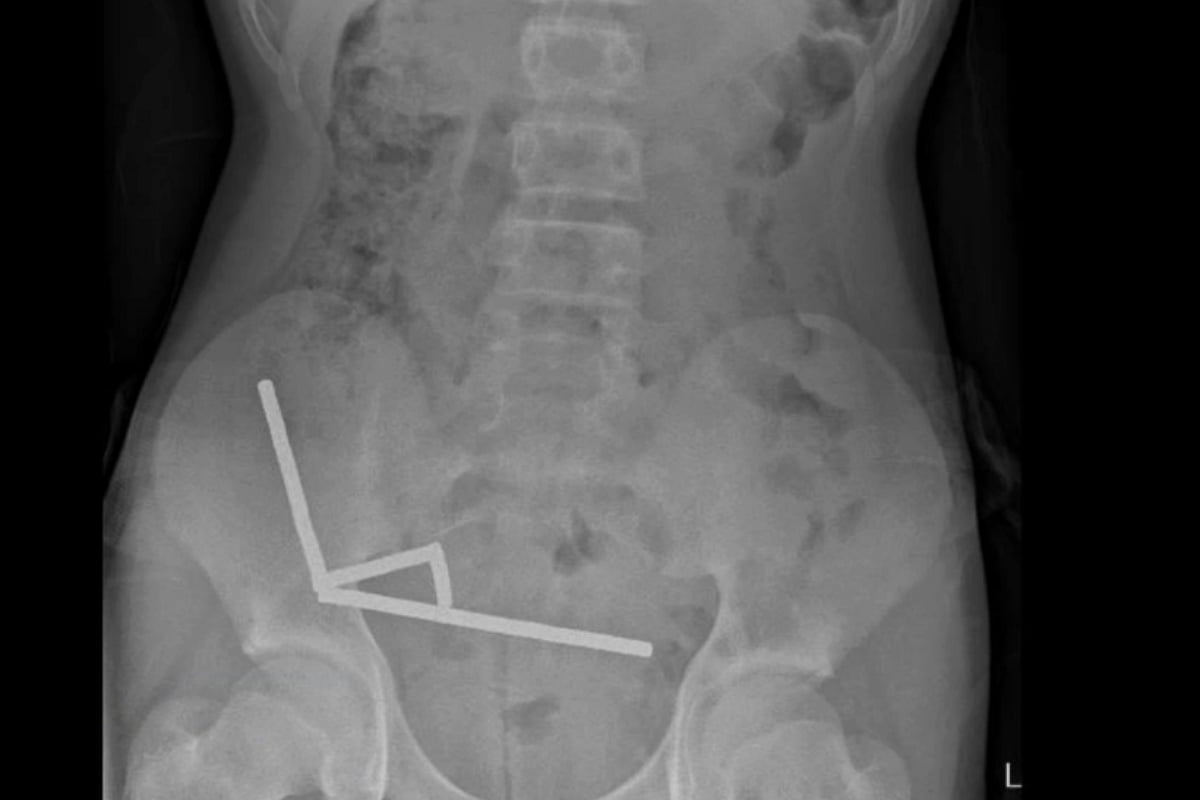

TUESDAY, Oct. 28, 2025 (HealthDay News) — A young boy in New Zealand needed emergency surgery and lost part of his bowel after swallowing more than 80 small, hi